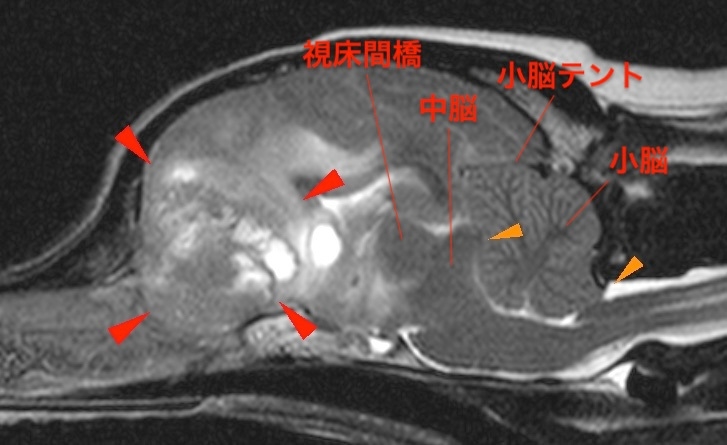

10歳、去勢雄の猫ちゃんで、 1年前からてんかん発作が続いているとのことでした。発作は抗てんかん薬などの内科治療ではコントロールできず、週3~4回発現していると…